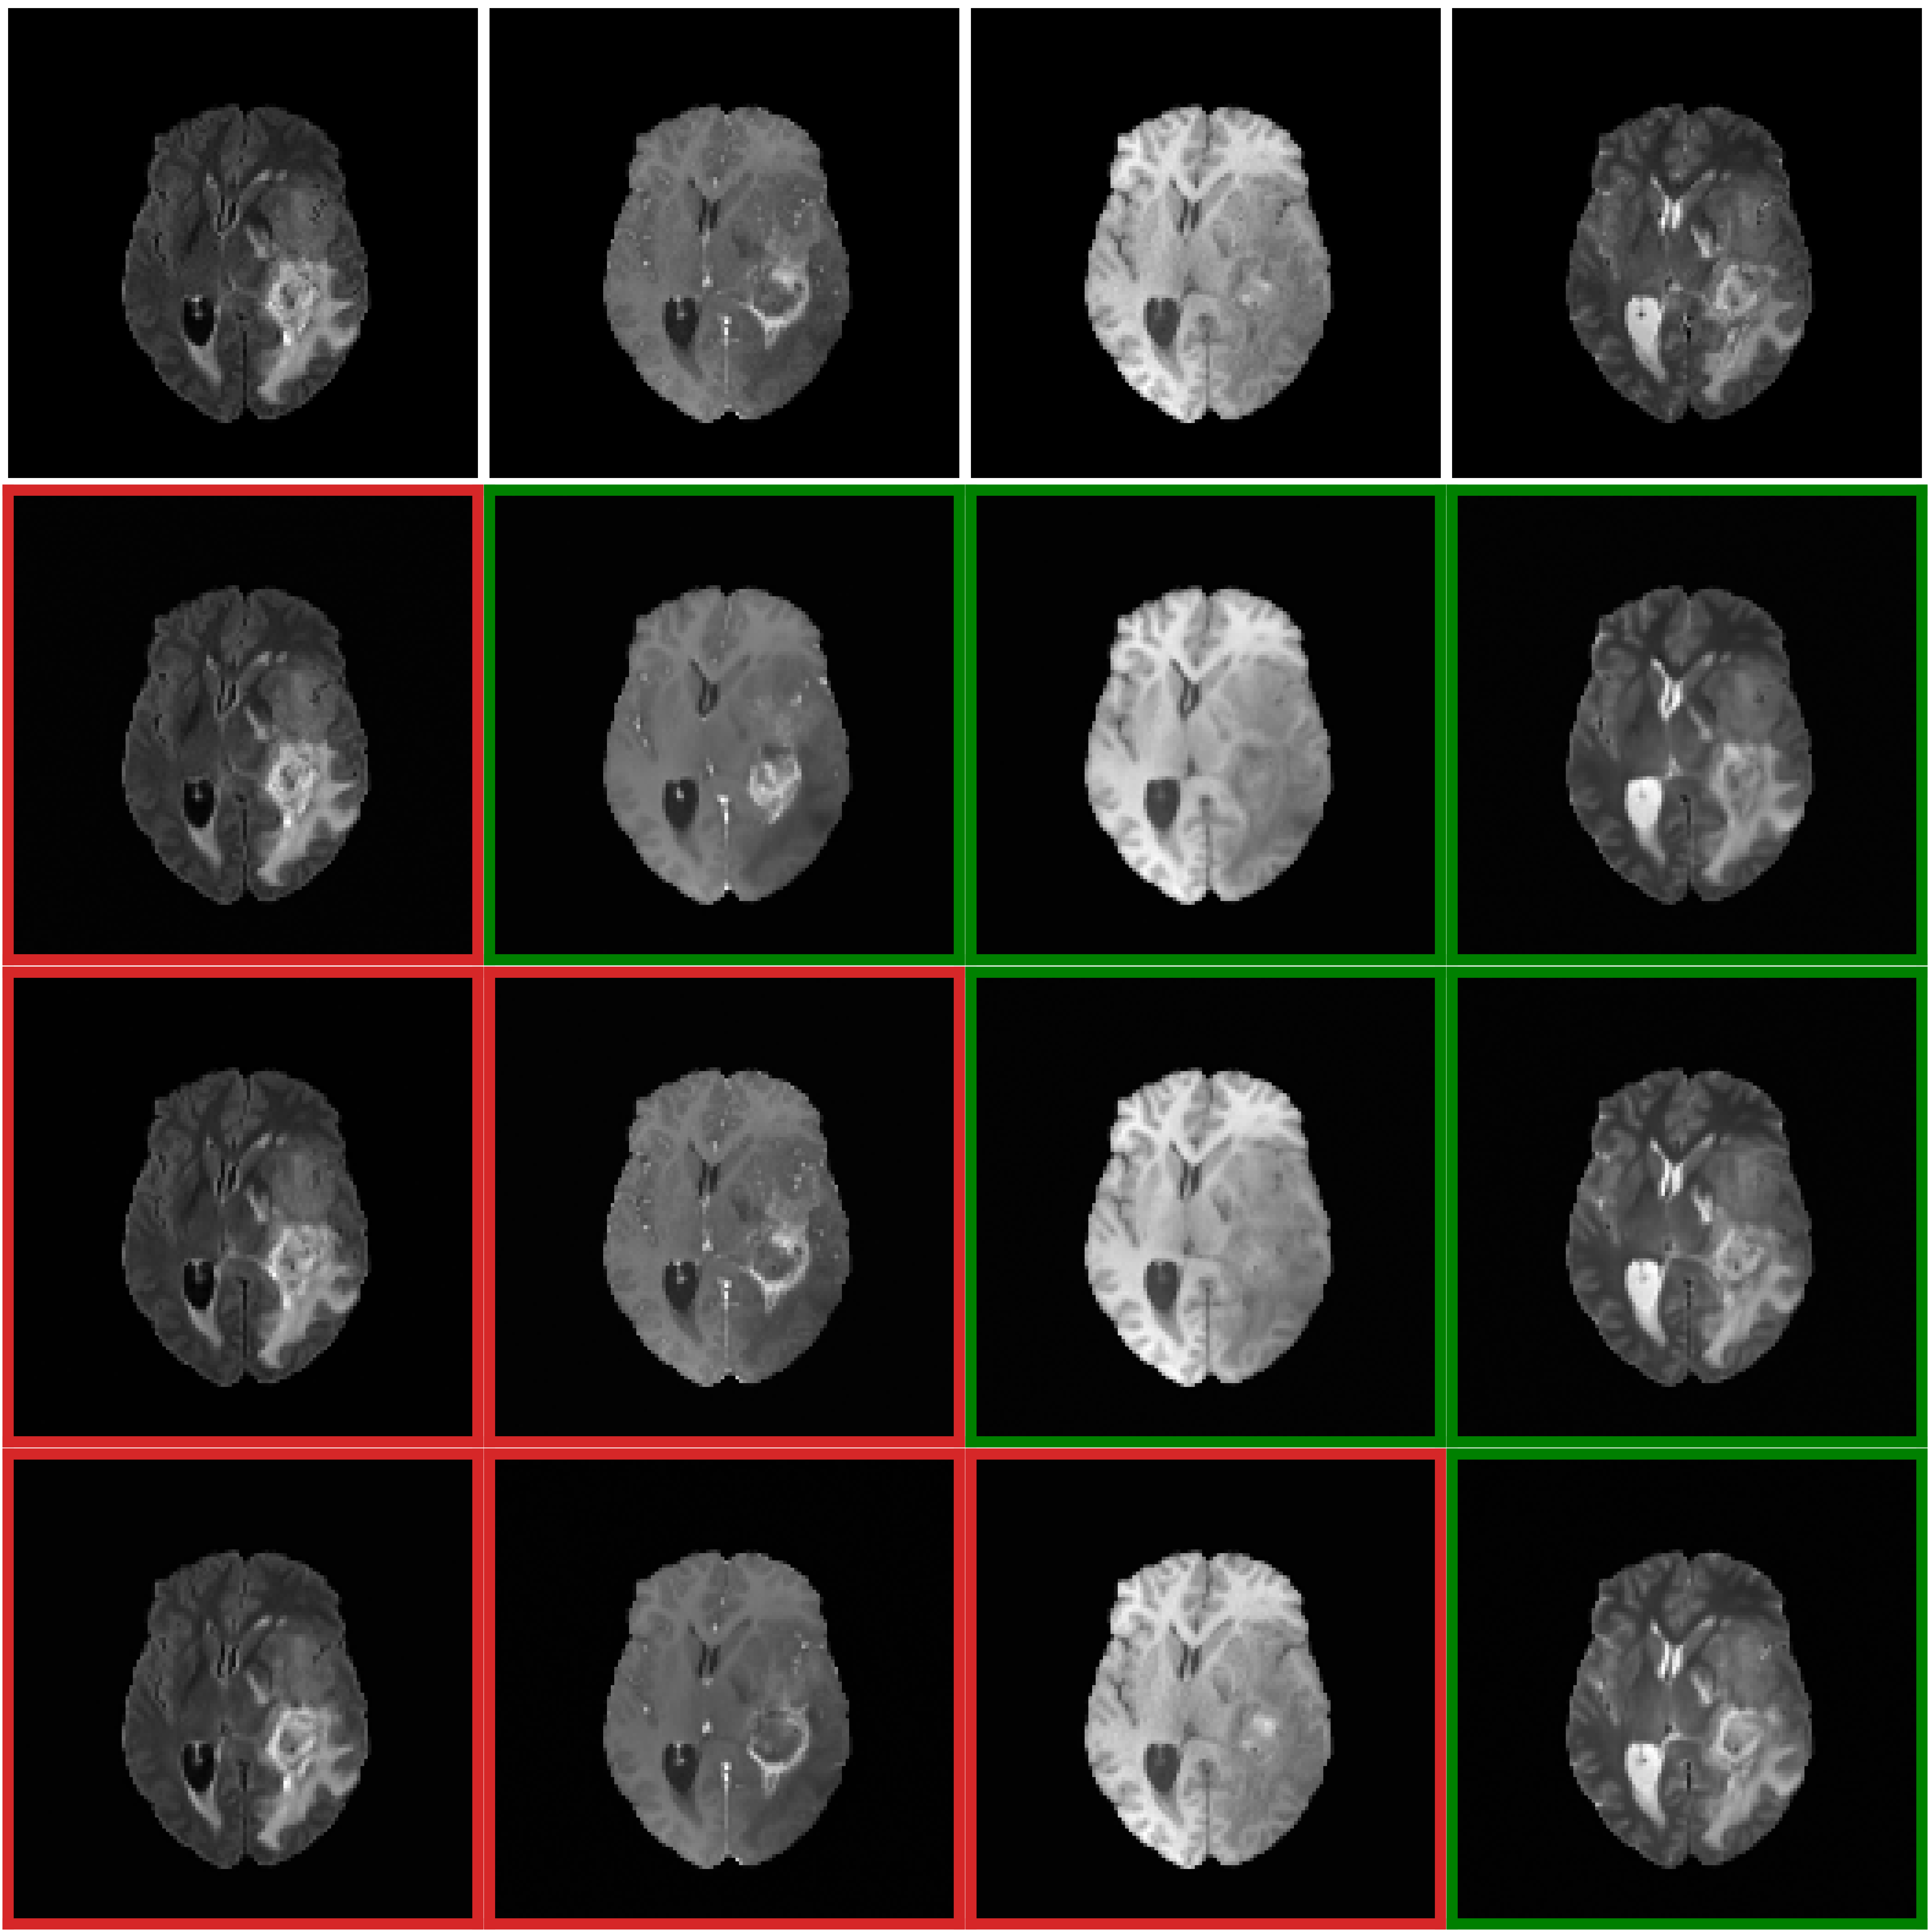

Refer to caption

Fig. 3: Illustration of adaptive translations from various input configurations. Red-bordered images represent inputs sequences and green-bordered images represent the predicted missing ones. See section 3.3.

Figure 2 shows qualitative comparisons of missing sequence translations generated by our method and the two other comparative methods. Our approach demonstrates more realistic and fine-grained details in the overall brain structure, with particularly precise tumor boundary representation compared to UMM-CSGM. The textural contrast between gray and white matter is also better preserved. Pix2Pix, on the other hand, exhibits missing fine-grained details and limited brain structure clarity. Each translation by our model was achieved using the same instance, underscoring its adaptability for dynamically generating missing sequences with high fidelity. In Figure 3, we present adaptive translations from various input configurations. The first row shows ground truth, while red and green borders highlight the input and synthesized sequences, respectively. A clear trend is observed: the more input sequences available, the richer the IFFN’s unified representation, particularly improving tumor delineation in T2 sequences from the second-to-last rows. However, when fewer input modalities are provided, there is a tendency for random interpolation of tumor regions, especially without key modality pairs like FLAIR/T2 or T1/T1CE. This is visible in the second row’s T1CE, which improves as more input sequences are added. Despite fewer inputs, our method reliably captures enough information to translate missing sequences, illustrating the robustness of the IFFN. Additionally, our approach, treating 3D images as a sequence of 2D slices, can easily extend to 3D image translation by processing each slice and reconstructing the full 3D volume.